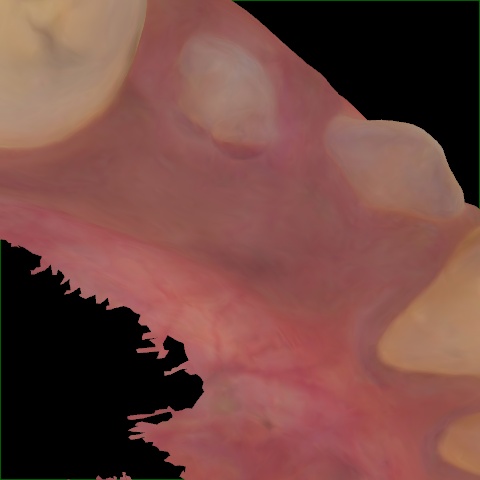

NHD25470

Annotated as "Good"